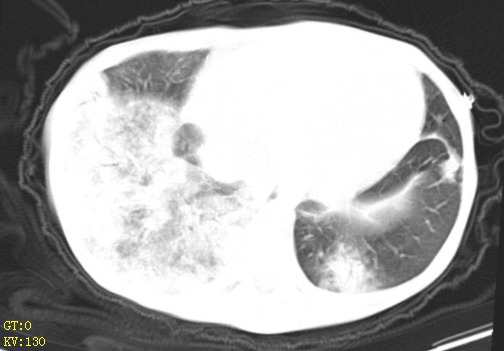

女,12岁,气促、咳嗽2天,3个月前查胸片示:两肺感染,急诊入院查ct,血常规等未检查。

双肺中下野不规则片絮状阴影,中外带明显,双侧胸腔少量积液,心影增大,心腔密度减低,隆突下及左侧气管旁见钙化淋巴结影,考虑双肺感染、心衰;建议结合临床除外h1n1并急性心衰,先心不能排除。

两肺多发片絮状模糊影,以下肺外带居多,内见支气管气像,纵膈窗未减影,两侧胸腔积液,心影增大,结合心超,支持重症肺炎,非常时期,甲型h1n1流感不排除。